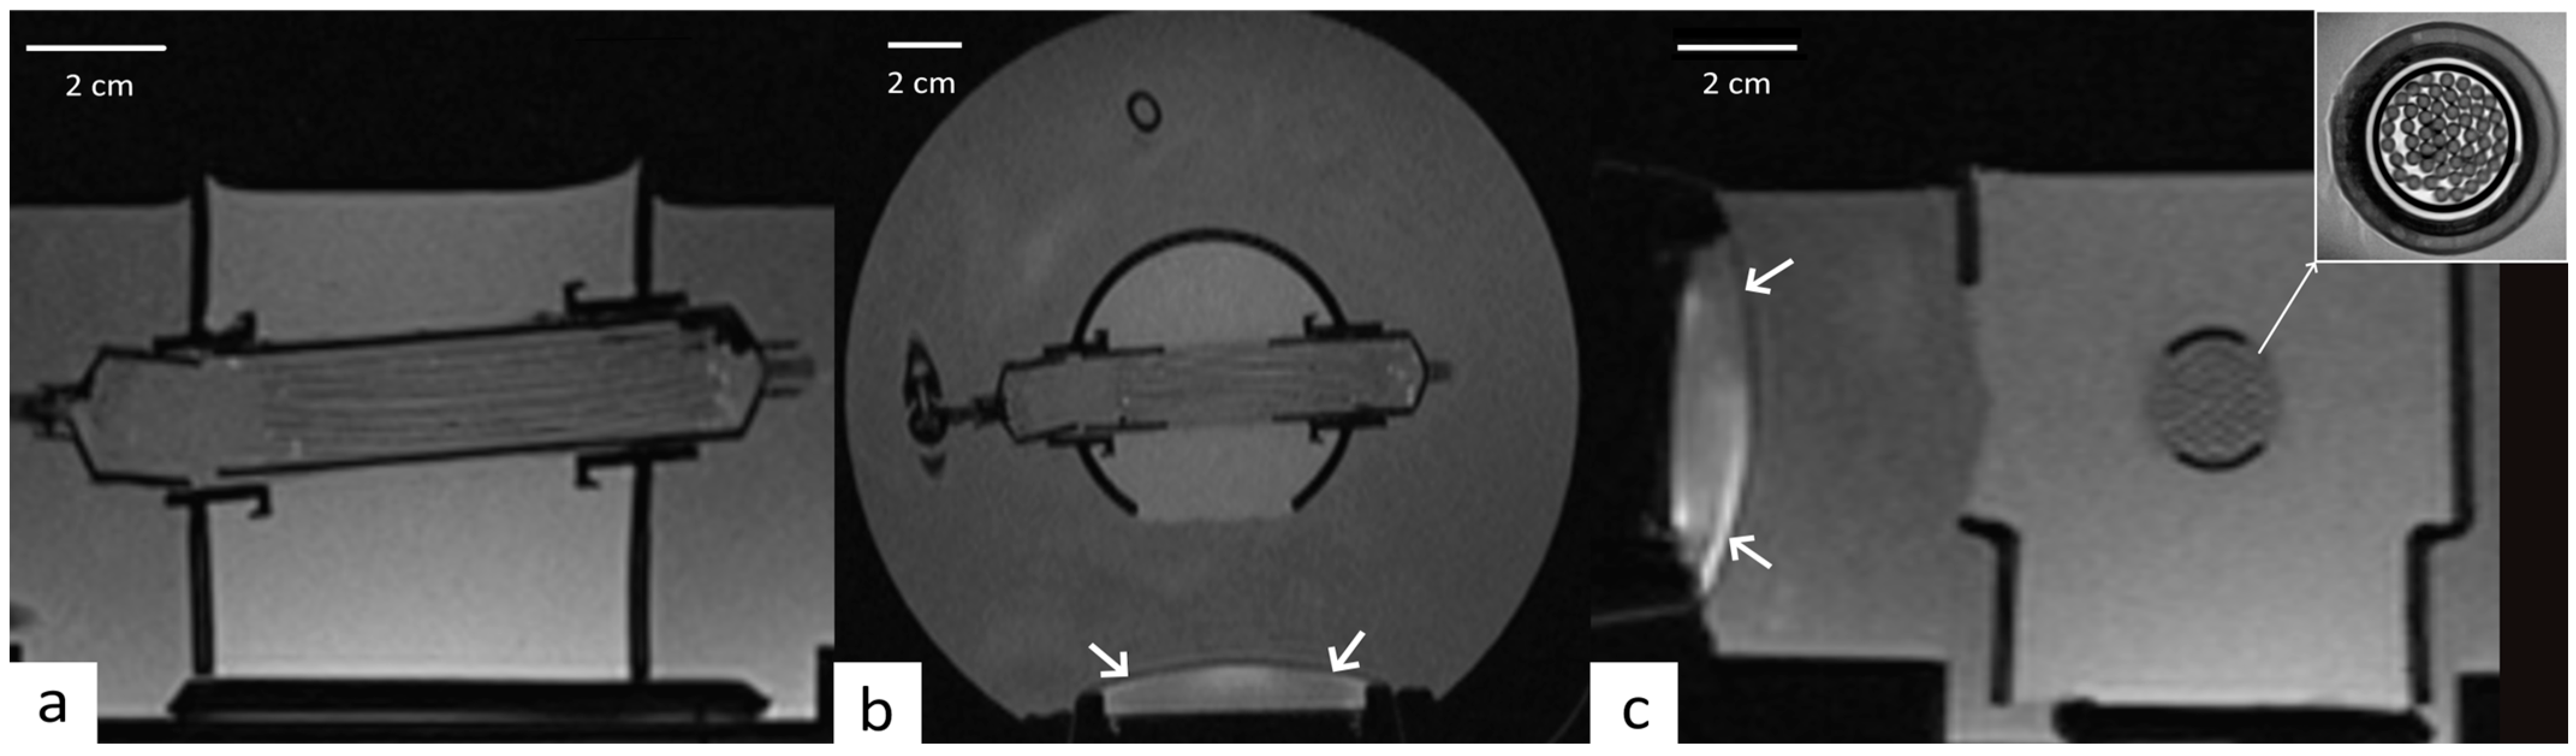

2.2. Perfused Phantom

2.3. MRI Guidance of Local Hyperthermia

2.4. Focused Ultrasound

2.5. Experimental Procedure on Perfused Phantom